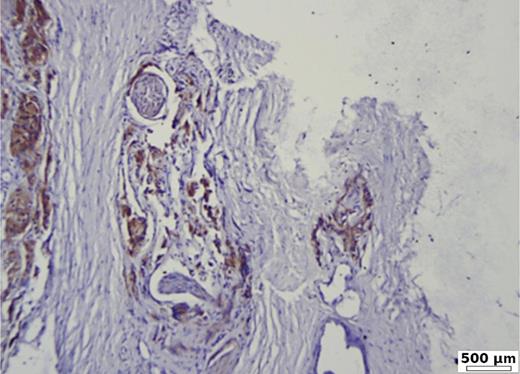

In the group of patients without carcinoma, the vast majority exhibited BSP expression of less than 1%. Twenty-nine out of thirty patients had a value below 5% (Table 1). One patient showed a BSP expression of 9%; however, the expression was observed only in basal cells in a condition of basal cell hyperplasia combined with chronic inflammation (Fig. 1). BSP expression in prostate tissue without carcinoma and without basal cell hyperplasia is shown in Figure 2.